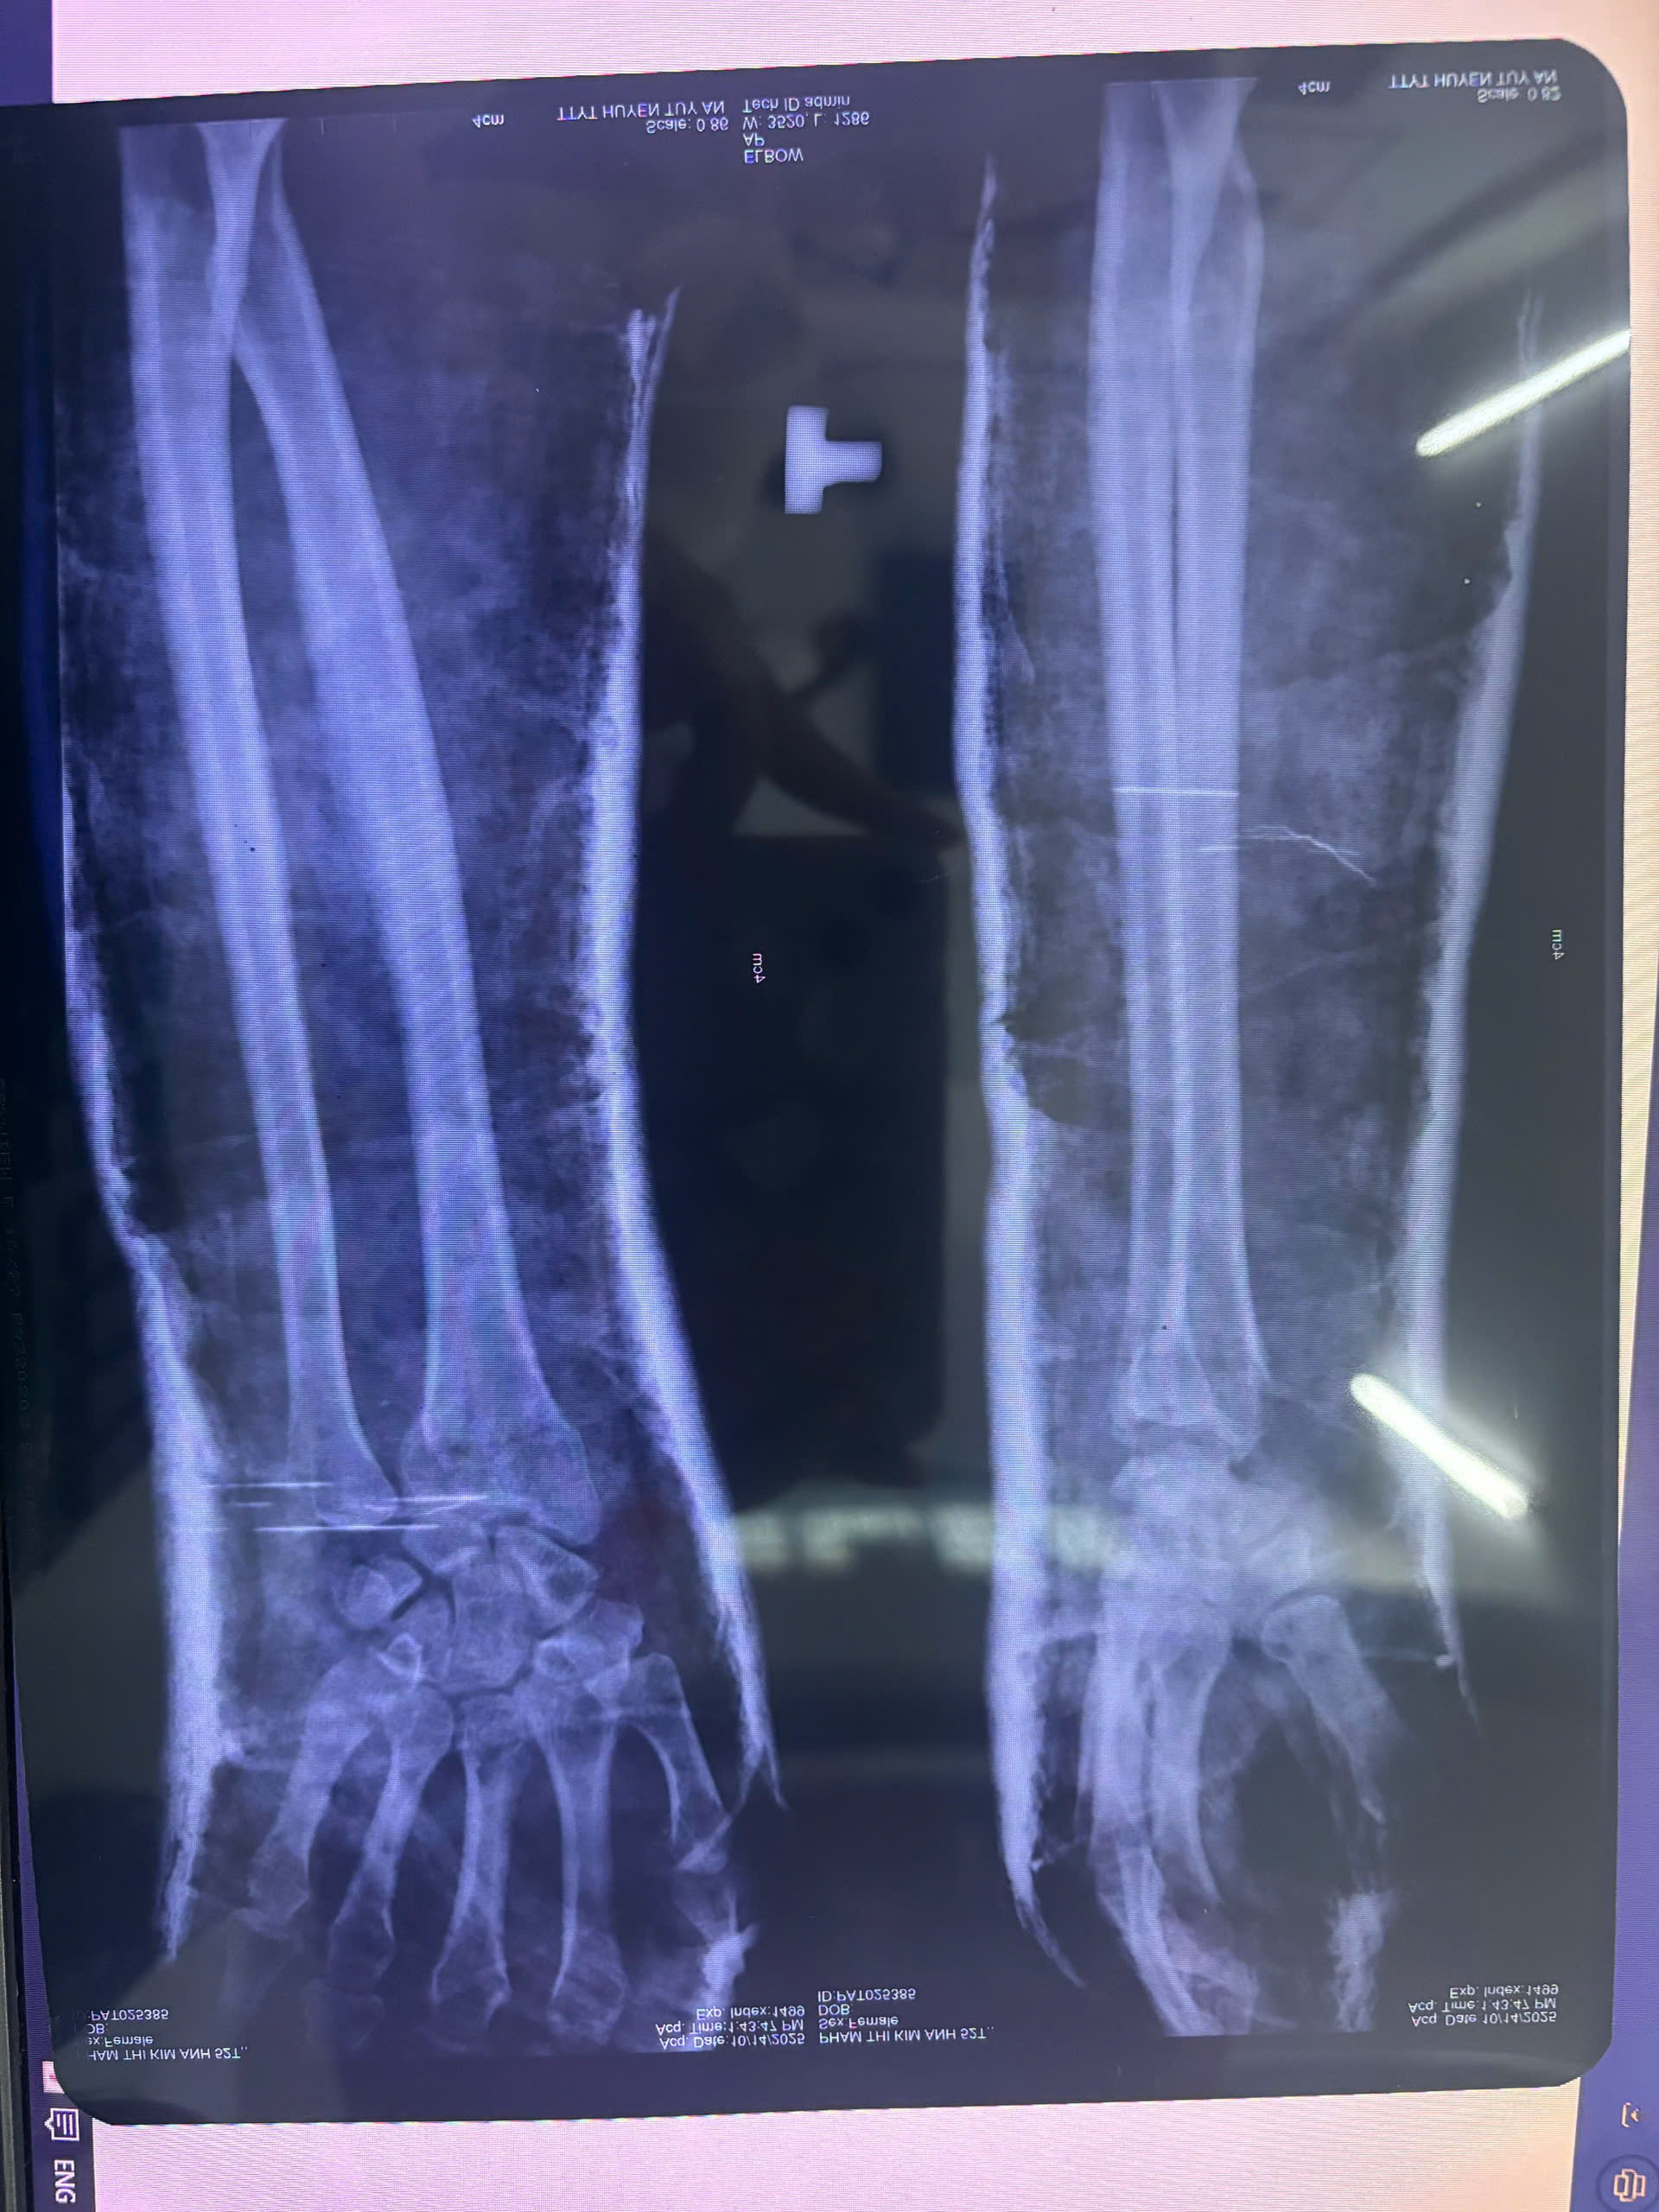

Trung tâm Y tế Tuy An nắn và bó bột cho bệnh nhân gãy đầu dưới xương quay trái